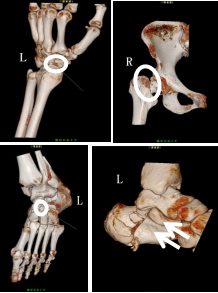

一般情况下,X线检查能够进行大多数骨关节外伤的检查,特别是对于四肢长骨的检查,有绝对的优势,但是,例如在手足、肋骨、颅骨等骨骼数量多、重叠度高的地方,相对来说,CT检查是一个很好的选择,特别是一些小部位撕脱骨折,能够清晰、明了的显示。

骨三维成像,是在CT扫描基础上进行三维成像检查,它能够提供任意角度地旋转观察受伤部位,详细了解人体各解剖结构的空间关系,更加直观、精确的显示病变,在骨关节外伤中应用中有着独特的优势。